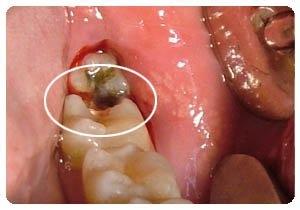

第三:对于龋坏较为严重的大面积缺损的牙,牙体修复后往往由于牙体本身抗力不足,在咀嚼时易发生牙折,为此,应避免进食硬物,以防牙折。

牙齿隐隐跳痛。如果牙齿龋洞很深,一直到了牙髓,那么就会出现这种疼痛,表明牙髓已经被感染。

如果充填物和牙齿釉质间粘接不密合,食物碎屑和致龋细菌会在缝隙内繁殖。您的牙很有可能还会出现另外一个龋洞,如果不及时治疗,就会伤及牙髓,甚至引起牙根尖部感染。